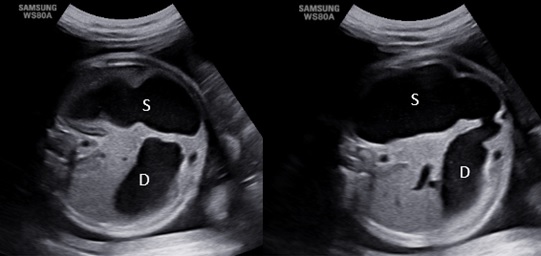

Hình ảnh kinh điển là bóng đôi thông nhau kèm đa ối. Hình bóng đôi là của dạ dày và đoạn gần tá tràng bị dãn rộng do teo hẹp tá tràng ở đoạn sau. Tiêu chí thông nhau là rất quan trọng để chẩn đoán tắc tá tràng, do đó người siêu âm cần di chuyển đầu dò để tìm hình ảnh thông nhau của bóng đôi.

Hình 1: Hình bóng đôi và bóng đôi thông nhau của dạ dày (S)và tá tràng (D)